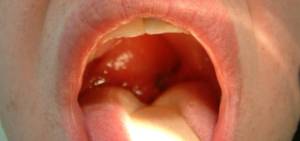

Peritonsillar Abscess (Quinsy)

- Uvula deviation